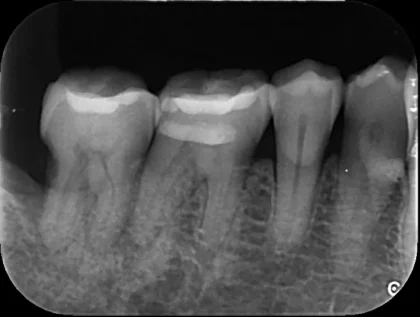

これは一般的なレントゲン写真とCTの部分的な画像です。

どうですか?レントゲンには写ってこないのですが、CTではハッキリと根の周囲に黒い影が見えます👀

これは2次元のレントゲンでは周りを厚い骨で囲まれている為に、根の病気が写らないのです。

レントゲン撮影